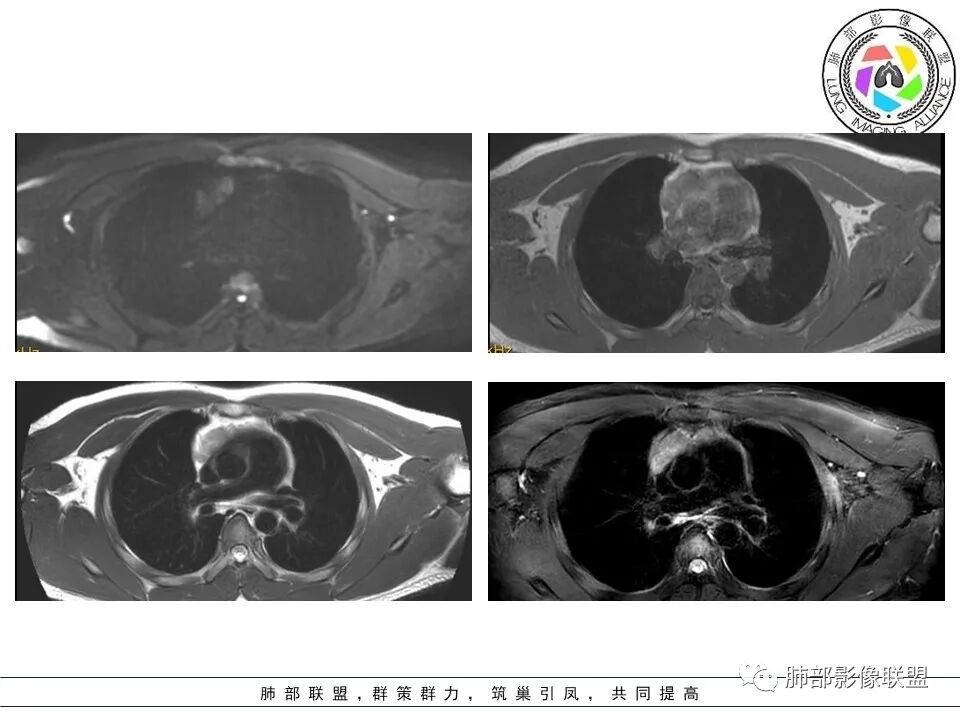

青少年男性,前纵隔结节,多结节间可见脂肪间隙,t2稍高,内见条状低信号,胸腺增生,淋巴瘤,生殖源性肿瘤

空格: 部分结节DWI高,T2有积液,不符合胸腺增生,还是淋巴瘤优先考虑。CT增强有环形强化。但DWI病灶中央也亮的,结核可能不大。

大家看看这病灶信号

看看这个内部结构

从MR看结构松散

不太符合肿瘤

DWI好像中央高一些

看这个图

就觉得内部结构松散

无肿瘤的特点